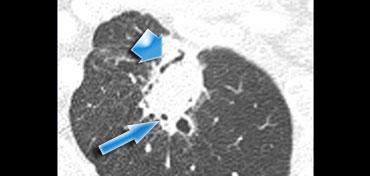

Dấu hiệu phế quản hơi

Các nghiên cứu gần đây cho thấy dấu hiệu phế quản hơi thường gặp hơn trong các nốt phổi ác tính.

Dấu hiệu này thường gặp nhất trong ung thư biểu mô phế nang (BAC – bronchoalveolar cell carcinoma) và ung thư biểu mô tuyến.

Trường hợp bên trái cho thấy dấu hiệu phế quản hơi biểu hiện dưới dạng vùng sáng dạng tuyến tính (mũi tên rộng) và dạng nang hơi (mũi tên nhỏ) do phế quản được nhìn theo trục dọc.